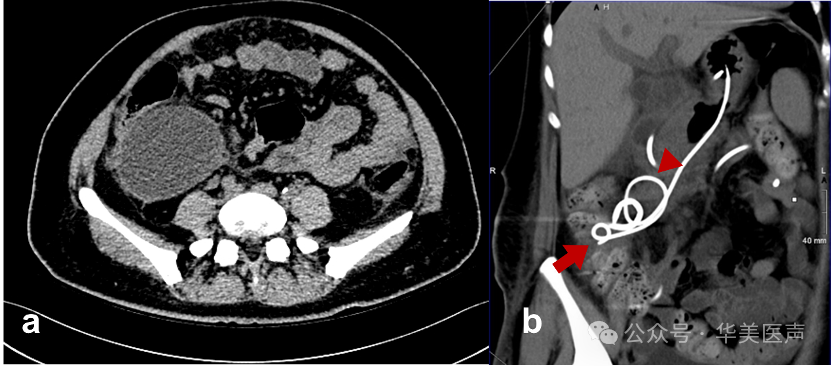

超声内镜联合ERCP确诊该患者为胰管断裂综合征(DPDS)。

我们先经胰管镜引导,但是导丝仍无法通过断裂胰管。经过讨论,我们遂行超声内镜引导下胰管穿刺引流术(EUS-PD)。

起初我们尝试将导丝导向十二指肠侧时发生导丝弯曲缠绕,未能实现胰管断端的桥接。故在囊腔与胃腔间留置7Fr塑料引流管,来引流囊腔液体。两周后囊肿基本消退。

我们又尝试了ERCP进行桥接,最终成功实现断裂胰管的桥接。